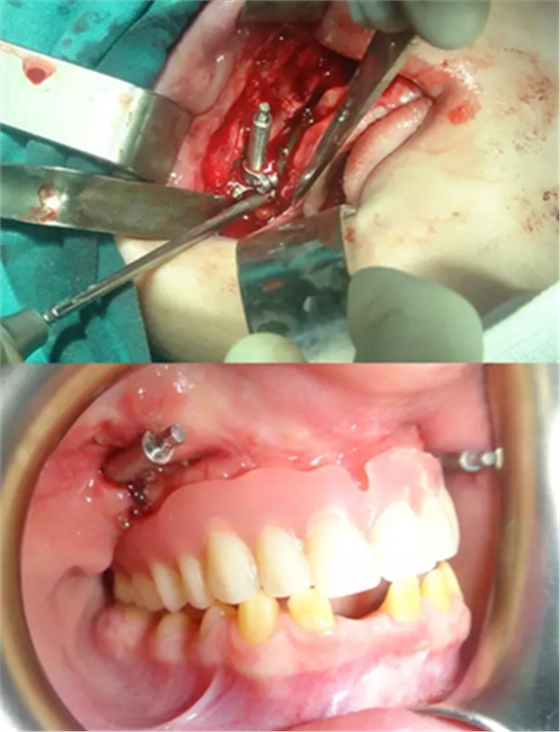

该患者的治疗目标是恢复牙颌面的正常功能和美观,包括颌骨的垂直关系及咬合关系。治疗步骤分别是术前诊断,制备引导性义齿,外科手术(Le FortⅠ型截骨牵张成骨),种植体植入及最终的义齿修复。上颌牵张 10 天(每天 0.5 mm×2 次),二期拆除牵张器并行种植体植入,术后出现轻微的感觉异常及开口困难,症状于 2 周后缓解。经头影测量可见 A 点、ANS 点、上唇、鼻尖点分别前移 6 mm、 8 mm、5 mm、2 mm。最后行义齿修复上颌牙列缺失。患者对最终的美观及功能恢复感到满意。

图 6. 安放牵张器及义齿引导